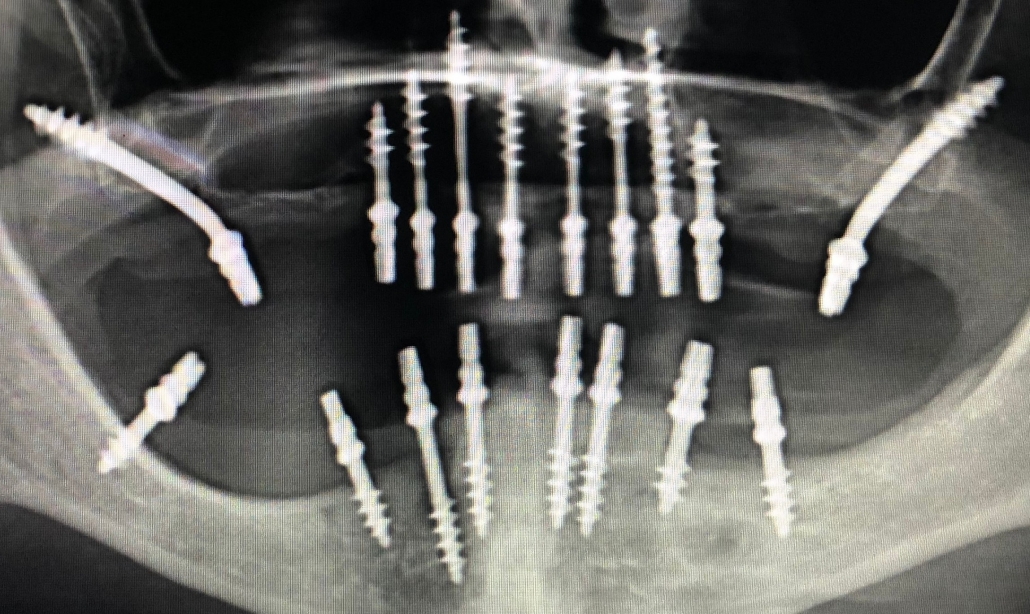

• Comprehensive Consultation & Planning: A detailed oral examination, digital scans, and OPG X-rays are taken to assess bone structure and plan the ideal implant position.

• Implant Placement: A titanium post is gently placed into the jawbone under local anesthesia — serving as an artificial tooth root.